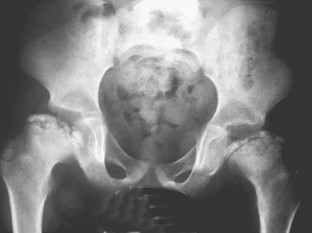

Abb. 4